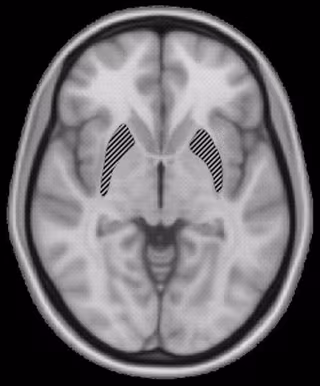

Los investigadores descubrieron que, en vez de residir en una única estructura, la inteligencia general está determinada por una red de regiones en ambos lados del cerebro.

Uno de los principales descubrimientos que impactaron a los científicos fue que existía un sistema distribuido y que varias regiones cerebrales, y las conexiones entre ellas, eran las más importantes para la inteligencia general.

"En realidad, las regiones y conexiones particulares que hallamos están bastante en línea con una teoría existente sobre la inteligencia llamada la 'teoría de integración parieto-frontal", explica el investigador. Esta teoría señala que la inteligencia general depende de la capacidad del cerebro para integrar varias clases diferentes de procesamiento, como la memoria de trabajo.